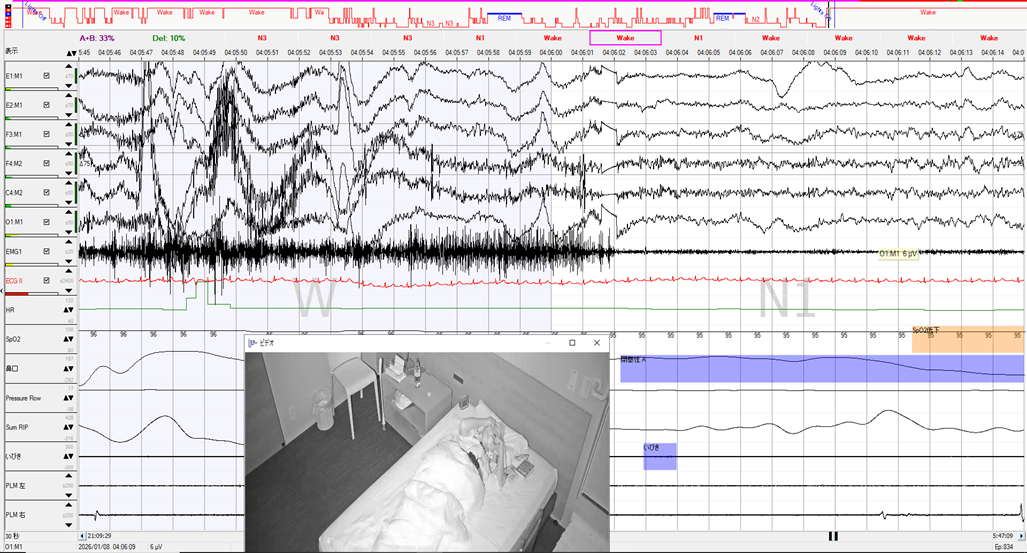

Wと判定したエポックはシールをはがしているときで、筋電図の混入が激しく、覚醒と判定していますが、直後は睡眠波形になっており、シールをはがしている間は覚醒ではなかった可能性があります。

しかしその時間帯はレム睡眠ではなく、シールをはがす直前は深睡眠であり(矢印部分)、スムーズに覚醒に移行できなかったと考えられます。